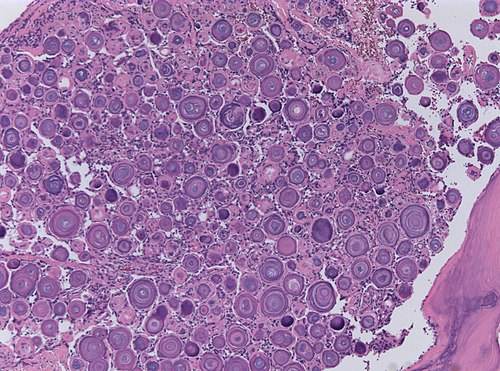

Exision of dura-based, calcified tumor.

Low magnification. H&E stain.

These round, calcified structures look like Psammoma bodies.

Psammomatous meningioma, WHO grade I

Comment: It is said, that psammoma bodies represent a process of dystrophic calcification or as an active biologic barrier to tumor spread ultimately leading to degeneration/death of tumor cells. [1] [2]